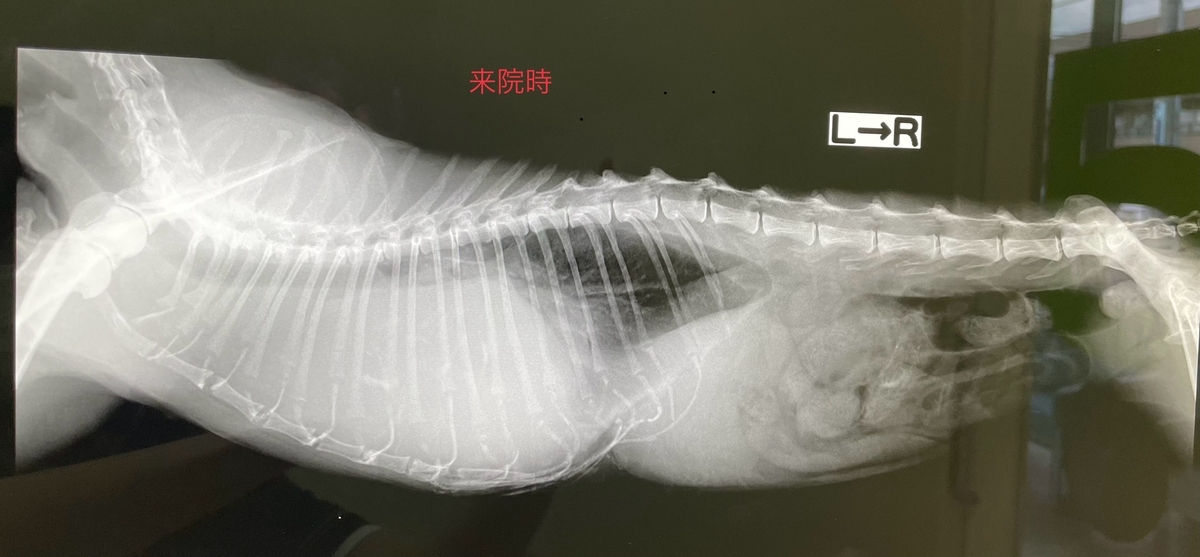

呼吸促迫、元気消失で来院された猫ちゃんが胸腺腫でした。

来院時胸水、前胸部に腫瘍病変があり、細胞診と胸水抜去を行いました。

この猫ちゃんは17才、CT検査にて線維素性胸膜炎の発症、腹側胸膜への浸潤、前大静脈、腕頭動脈、右心房と癒着しており、手術のリスクが高い為、緩和治療となりました。